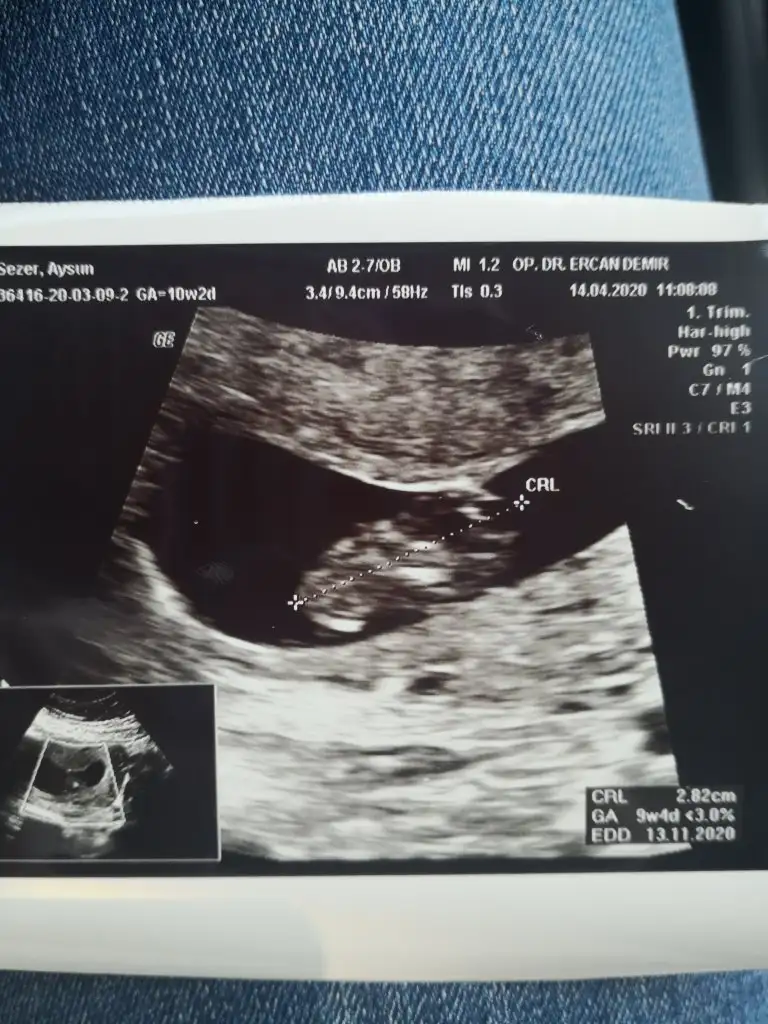

8 hafta ya göre erkek ama siz 11 12 13 hafta nub için paylaşınbize de tahmin yaparmısınız. ikisi de karından usg. ilk resim 9+4 ikincisi 8

Buna göre kızKarindan usg 7+4kizlar yorum yapacak olan varsa cok mutlu olurum

Merhaba bizim de 13. Hafta böyle sizce nedir :)Slm arkadaşlar nub teorisi konumuzda yaptıgım tahminleri ankete tıklayın yuzdesini görelim